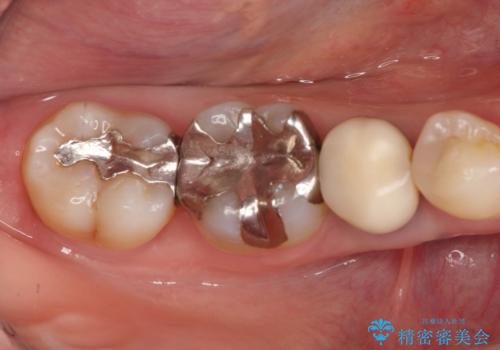

- 笑った時に見える金属を白くしたいとのことでメタルフリーの治療を希望され来院されました。

根管治療を行なったのち、オールセラミッククラウンにて修復処置を行っております。